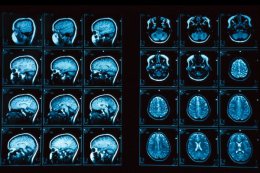

Исследователи определили общий генетический вариант – изменения в генетическом коде человека – связанный с тем, как быстро человек способен обработать новую информацию.

Скорость обработки информации считается основной возможностью для сохранения умственных навыков в пожилом возрасте. По словам ученых, что открытие может помочь понять, как работает мозг, и почему некоторые люди переживают снижение умственных способностей, в то время как с другими этого не происходит.

Было установлено, что люди с более медленной скоростью обработки информации имели варианты гена под названием CADM2. Ген CADM2 участвует в процессе коммуникации между клетками мозга и особенно активен в лобной и поясной коре головного мозга, которые являются областями, участвующими в скорости мышления.

Идентифицированный генетический вариант отчасти объясняет различия в скорости обработки информации между людьми. Проведенное исследование подтверждает возможную роль гена CADM2 в межклеточной коммуникации и, следовательно, когнитивных функциях, говорят ученые.